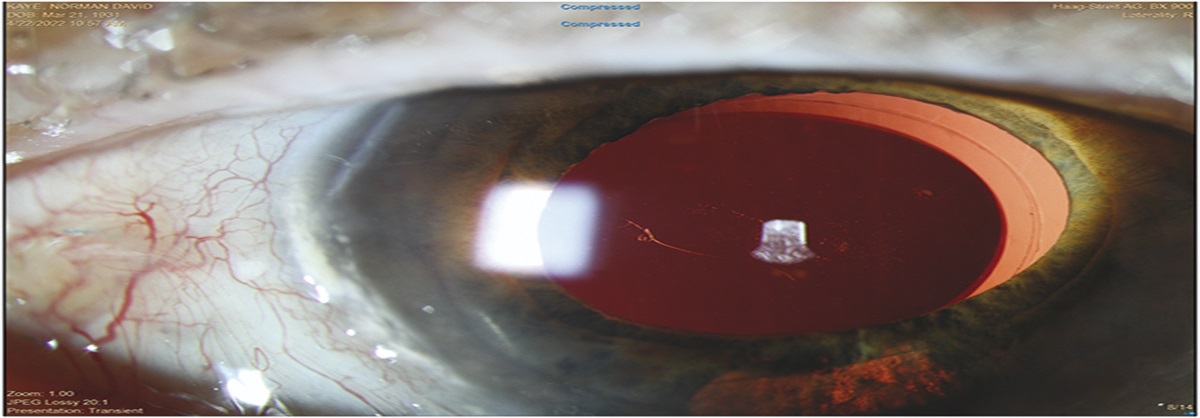

Alternative Techniques To Remove Retained Silicone Oil Droplets On IOLs

Background/Purpose: To describe several modified approaches to remove retained silicone oil dropl